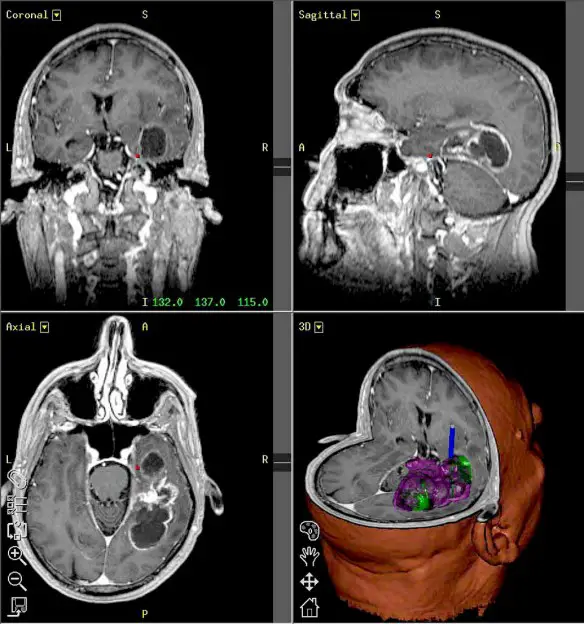

Il virus della poliomielite guarisce uno dei tumori cerebrali più maligni: il glioblastoma multiforme

Il glioblastoma (noto anche come glioblastoma multiforme) è un tumore tristemente noto per essere il più comune e più maligno tra le neoplasie delle cellule della glia (le cellule che, assieme ai neuroni, costituiscono il sistema nervoso). Purtroppo è un tumore che raramente permette una lunga sopravvivenza del paziente. Ma ora sembra che ci sia una speranza per tutti gli affetti da questa perfida patologia: il virus della poliomielite. È il network statunitense Abc a raccontare la storia di Stephanie Lipscomb, 22 anni, cui due anni fa è stato diagnosticato un glioblastoma, una delle forme tumorali più aggressive che possono colpire il cervello.